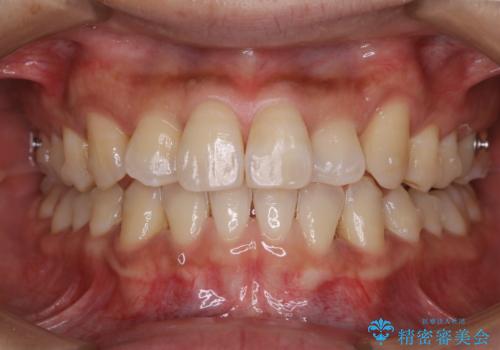

マウスピース矯正の途中にPMTCで白い歯に

- インビザラインによるマウスピース矯正中に歯の黄ばみ・ステインが気になるとのことでした。PMTC60分コースを行いました。

マウスピース矯正インビザライン治療では、歯の表面にアタッチメントという突起を設定します。(アタッチメントは歯の動きを効率的に移動するためのものです)

アタッチメントが歯に付くと、表面が凸凹し磨き残しが多くなったりと、プラークや歯石・着色がつきやすくなることがあります。

矯正治療中もPMTCを定期的に行い、専門的な機械でしっかりと汚れを除去することがおススメです。